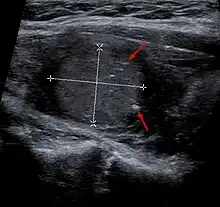

![]() | |

| Micrograph of medullary thyroid carcinoma with amyloid deposition (left of image). Near normal thyroid follicles are also seen (right of image). H&E stain. | |